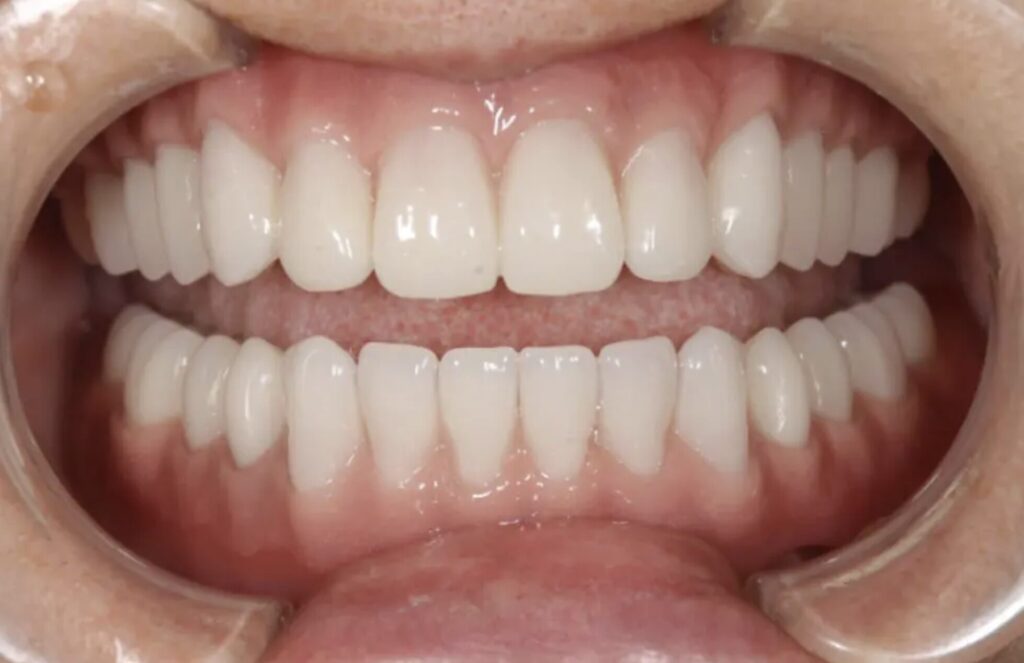

「入れ歯では噛めない」からの解放|インプラントオーバーデンチャーで劇的改善した症例

60代女性の患者様は、「左上のブリッジが外れかけている」「歯がないところに歯を入れたい」というお悩みで来院されました。長年ご両親の介護を優先し、自分の歯の治療を後回しにされていたそうです。これまで入れ歯での生活に不自由を感じていたことから、しっかり噛める治療を希望。診断の結果、上顎は総義歯、下顎はインプラントオーバーデンチャーで治療を行いました。静脈内鎮静下でのオペにより、恐怖や痛みを抑えながら、安全に手術を実施。治療後は噛み心地・見た目ともに大きく改善し、入れ歯では得られなかった安定感と自信を取り戻された症例です。